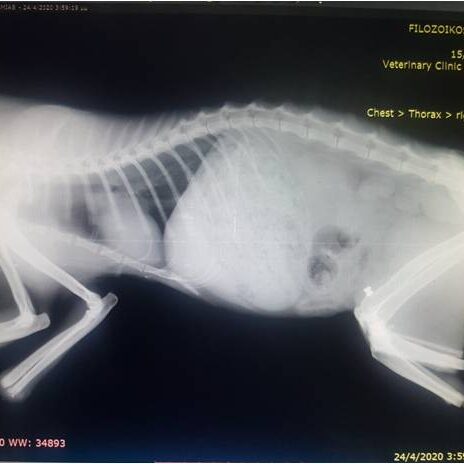

Η διαδικασία ξεκινά με μία αξονική τομογραφία στο Ιατρικό μας κέντρο στην Λευκάδα ή σε κάποιο συνεργαζόμενο με τον κτηνίατρο σας ιατρικό κέντρο. Μέσω αυτής λαμβάνουμε τα απαραίτητα CΤ-images όπου γίνεται ανάλυση  ψηφιακών δεδομένων με χρήση εξειδικευμένου ιατρικού λογισμικού Osirix-FDA.

Το επόμενο στάδιο είναι αυτό της προ-εγχειρητικής μελέτης-διάγνωσης, με σύγχρονες μεθόδους και εξοπλισμό όπως:

Η διαδικασία ολοκληρώνεται με την χειρουργική επέμβαση όπου το εμφύτευμα, τοποθετείται στο ακρωτηριασμένο οστό. Το χειρουργημένο άκρο θα πρέπει να προστατευθεί για 5-6 εβδομάδες πριν από την εφαρμογή του έξω-προσθετικού. Σύμφωνα με αποτελέσματα περιστατικών άλλων χωρών, η βιολογική ενσωμάτωση των οστικών και δερματικών ιστών με εμφύτευμα τύπου ITAP κρίθηκε αξιόπιστη και ανθεκτική.